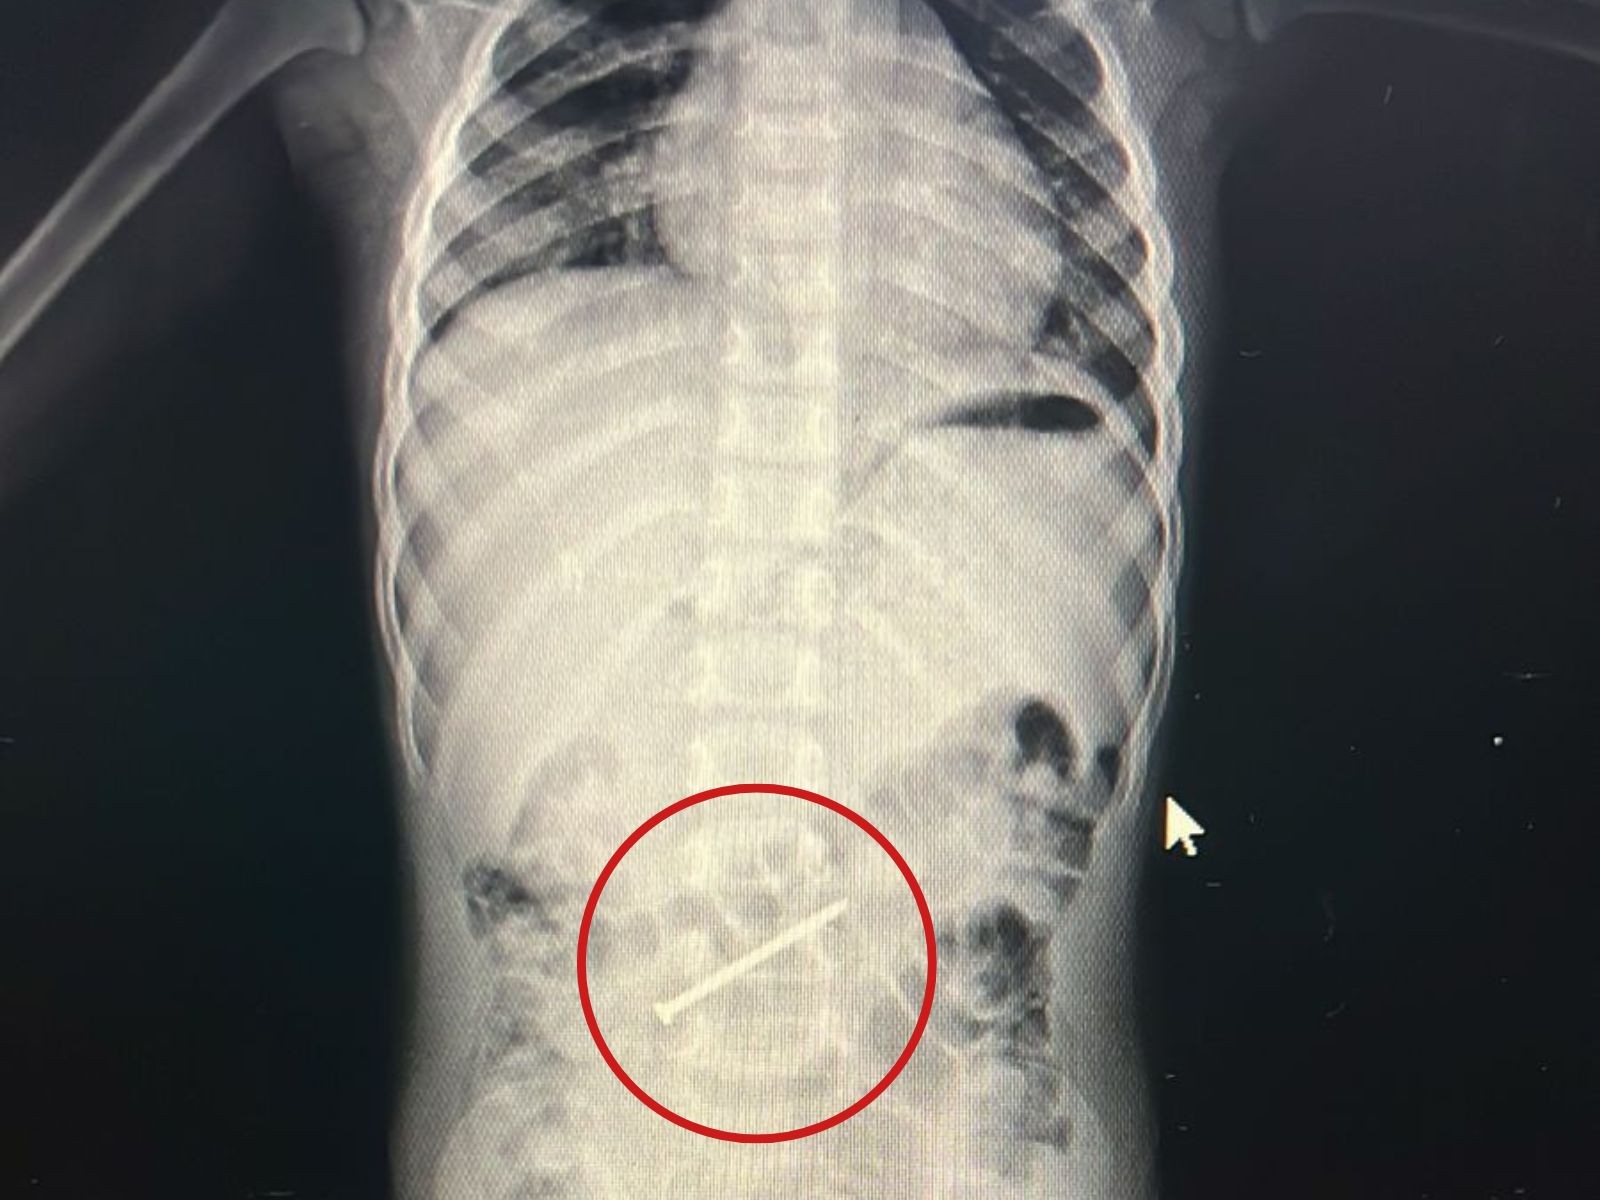

Menino de 3 anos passa por colonoscopia para retirada de prego no intestino no AC

16/01/2026 - Prego estava no intestino grosso da criança

Um menino de 3 anos passou por uma colonoscopia na tarde desta sexta-feira (16) no Hospital Regional do Juruá, em Cruzeiro do Sul, interior do Acre, para retirada de um prego do intestino grosso. A criança está internada desde a última quarta (14) e passa bem.

O menino é de Ipixuna, cidade do Amazonas, e foi levado para Cruzeiro do Sul, junto com a mãe, para ter um atendimento especializado. O prego tinha seis centímetros.

Ao g1, o cirurgião e endoscopista Marlon Holanda, que participou do procedimento de retirada, contou que o menino ficou em observação durante dois dias para que fosse decidido o procedimento mais indicado de retirada.

"É um objeto pontiaguado, havia o risco de perfurar o intestino. Como não estava descendo, ficou parado dois dias no mesmo lugar, optamos pela colonoscopia. Foi um procedimento tranquilo", destacou.

Ainda segundo o médico, a mãe contou que a criança brincava com uma caixa de ferramenta e acabou colocando o prego na boca. Logo de imediata, a mulher procurou ajuda médica no município onde vive.